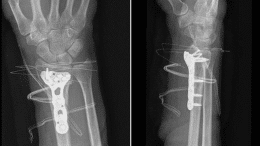

Distal Radius Fractures in Adults

Summary Distal radius Fractures are the most common injury in adults. They involve traumatic lesions of the distal ulna and radius and the proximal carpal…